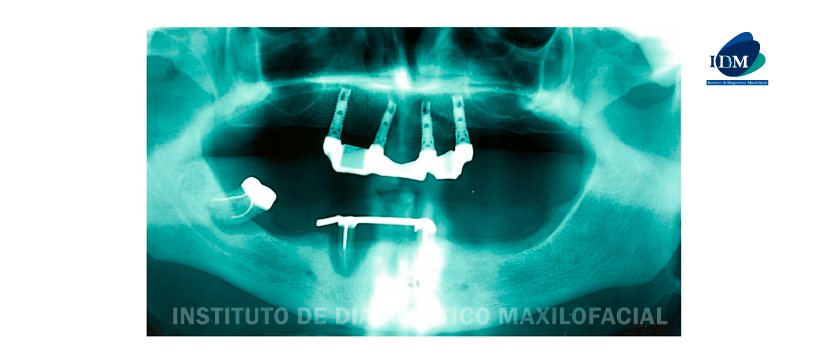

El historial dental anterior del paciente reveló extracciones del primer molar derecho mandibular y de ambos caninos mandibulares debido a lesiones periapicales, con legrado del tejido de granulación (Figura 1). Cinco meses después de las extracciones dentales, se propuso un proyecto terapéutico basado en implantes (Figura 2 (a)) y la Figura 2 derecha (b ) sinfisias mandibulares. Luego se colocaron dos implantes dentales osteointegrados.

Los implantes se sumergieron y se dejaron en su lugar durante un período de tres meses. Una semana después, el paciente fue derivado a una consulta de emergencia por dolor facial. El examen clínico reveló inflamación difusa de la región submandibular, que era firme y dolorosa, con enrojecimiento de la piel. El paciente también informó parestesia labiomandibular.